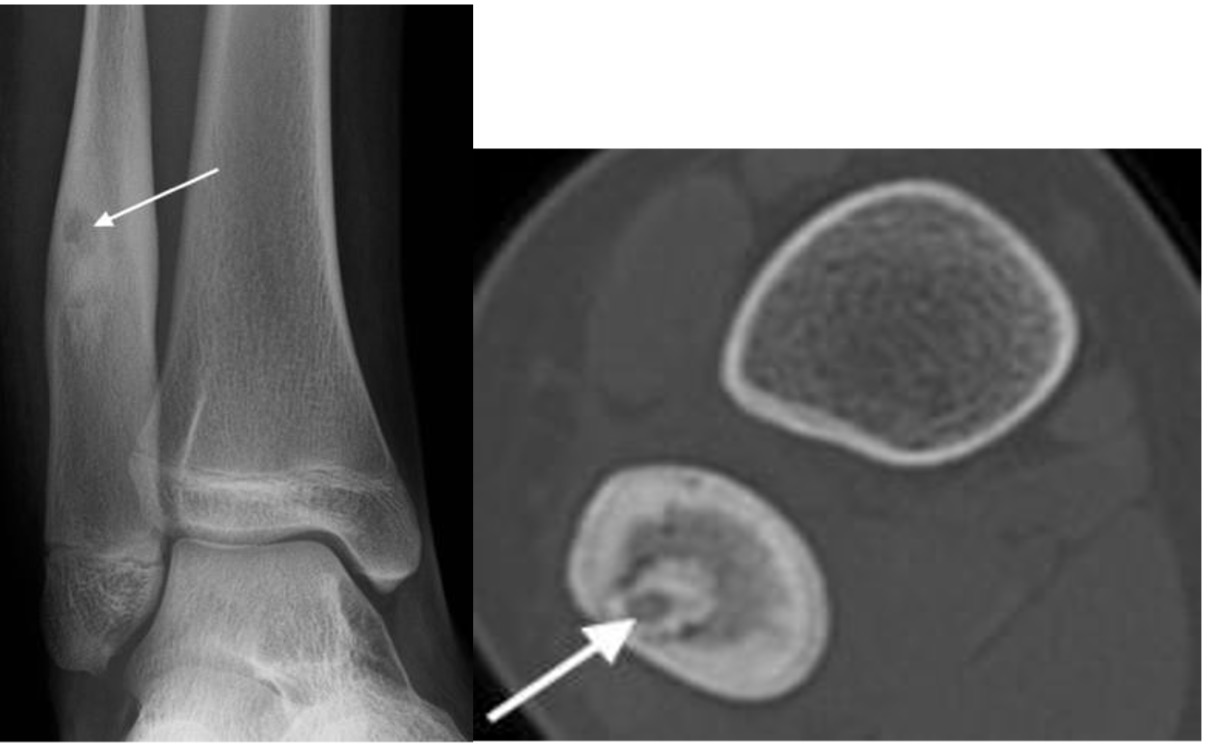

Osteoid osteoma

- Typically in young patients who complain of severe rest and night pain

- Dramatic relief with aspirin

- Seen as ovoid radiolucent nidus up to 1cm in diameter surrounded by sclerosis and periosteal thickening

- Sclerosis may mask the radiolucent nidus on plain radiographs; best seen on thin CT sections

Osteoid osteoma with radiolucent nidus (arrows) and surrounding sclerosis best seen on CT